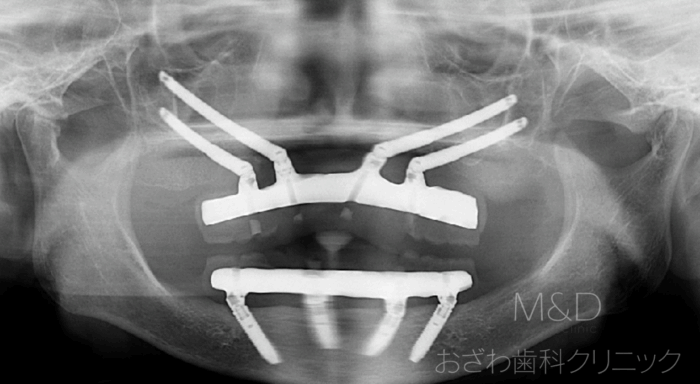

術後

上顎は4本のザイゴマインプラント(頬骨インプラント4本)下顎はオールオン4による治療後

即時負荷(手術当日に仮の歯が入り噛むことができます)

上顎はザイゴマインプラント(頬骨インプラント)、下顎はオールオン4による治療後

即時負荷(手術当日に仮の歯が入ります)

上顎前歯にはインプラントを埋める骨が全くありません

大学病院で断られた患者さん

通常のインプラントができない場合、頬骨のみを利用したインプラント治療になります